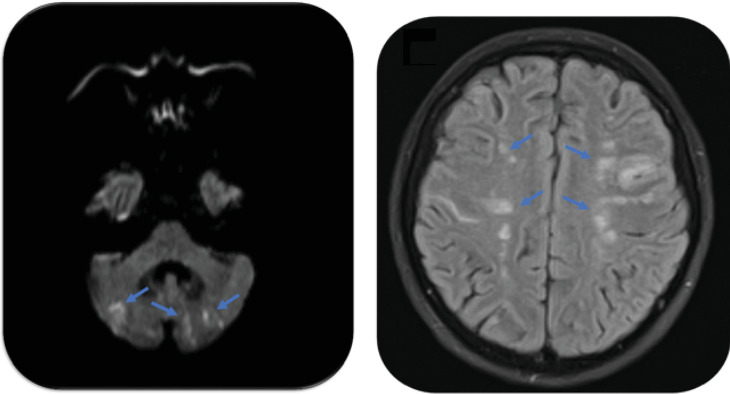

非细菌性血栓性心内膜炎是一种罕见的疾病,其特征是在心脏瓣膜上形成非感染性植物。它与系统性栓塞现象有关,主要发生在癌症晚期,特别是腺癌。这是一种基于临床背景的排除诊断,超声心动图显示的植被,阴性血培养,和感染性心内膜炎之间的区别是具有挑战性的。我们报告一个病例66岁的妇女,既往治疗乳腺和尿路上皮癌的历史,提出了体质综合征和肺血栓栓塞。计算机断层扫描显示全身栓塞现象和腹膜后淋巴结病变。在超声心动图上发现二尖瓣的植被,引起严重的二尖瓣反流,导致严重的急性心力衰竭,最终导致患者死亡。随后的淋巴结活检免疫组化结果显示尿路上皮癌复发。

Nonbacterial thrombotic endocarditis is a rare condition characterized by the formation of noninfectious vegetations on the heart valves. It is related with systemic embolic phenomena occurring predominantly in advanced cancer stages, particularly adenocarcinomas. It is a diagnosis of exclusion based on the clinical context, echocardiographic findings of a vegetation, and negative blood cultures, and distinction between infective endocarditis is challenging. We report a case of a 66-year-old woman, with history of previously treated breast and urothelial carcinoma, presenting with constitutional syndrome and pulmonary thromboembolism. Computed tomography scan revealed systemic embolic phenomena and retroperitoneal lymphadenopathies. A vegetation in the mitral valve constituted a finding on echocardiography, causing severe mitral regurgitation, which led to severe acute heart failure and culminated in patient's death. Subsequent results of immunohistochemistry of the lymph node biopsy yielded the recurrence of urothelial carcinoma.